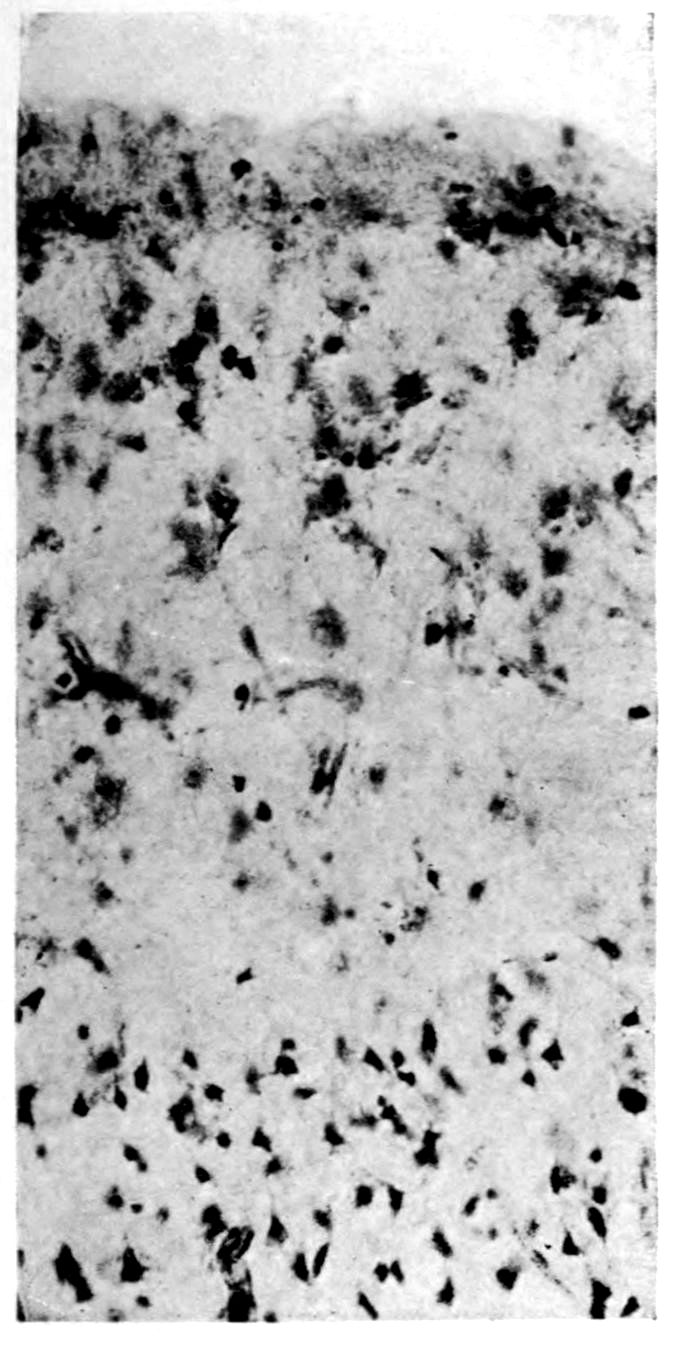

A. Normal postcentral cortex. (Compare B.)

B. Nerve cell losses. Perivascular deposits of mononuclear cells, amongst which are numerous plasma cells. Note decrease in number of nerve cells. Note irregular disposition of nerve cells. From paretic neurosyphilis.